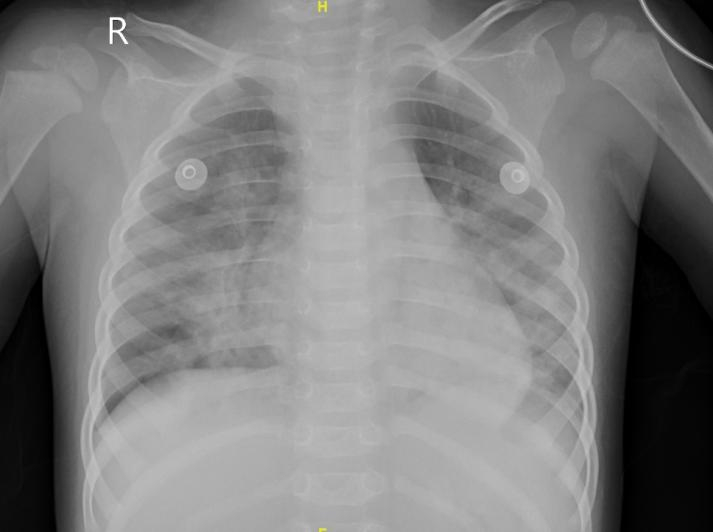

查体:体重13 kg,体温36.9 ℃,心率160次/min,呼吸频率45次/min,血压103/62 mmHg(1 mmHg=0.133 kPa),经皮血氧饱和度95%;镇静状态,双侧瞳孔等大等圆,直径3 mm,对光反应稍迟钝;呼吸急促,伴有喉中发声,双肺呼吸音粗,可闻及粗湿啰音;心律齐,心音有力,腹软,肝脾肋下未及双巴氏征阳性。辅助检查:血常规示白细胞3.86×109/L,红细胞4.62×1012/L,血红蛋白113 g/L,中性粒细胞比率52.8%,淋巴细胞比率41.2%,血小板225×109/L,C-反应蛋白52.1 mg/L,降钙素原13.72 ng/mL,胆碱酯酶5 739 U/L。血气分析示酸碱度7.26,二氧化碳分压46.3 mmHg,氧分压89.6 mmHg,乳酸1.6 mmol/L,碳酸氢根19.2 mmol/L,碱剩余6.4 mmol/L;血生化示:丙氨酸氨基转移酶18.7 U/L,天门冬氨酸氨基转移酶60.7 U/L,肌酐27.2 µmol/L,肌酸激酶165 U/L,肌酸激酶同工酶5.17 ng/mL,肌钙蛋白T 0.052 ng/mL,N端-B型钠尿肽前体149.2 pg/mL,神经元特异性烯醇化酶33.36 ng/mL,白介素-6 153.5 pg/mL,血钙2.03 mmol/L,血钾3.79 mmol/L,血钠136.5 mmol/L,血糖6.85 mmol/L。床边胸片示双肺纹理增多模糊、可见斑片状影(图 1);心电图、心脏彩超未见异常;脑脊液常规检测未见异常。血液、尿液标本行毒物筛查结果显示血液中四氟苯菊酯浓度为20 ng/mL,尿中监测到四氟苯菊酯;视频脑电图示背景活动异常,双侧后头部为主3-5Hz中-高波幅混合慢波活动,夹杂多量低波幅快波,左右大致对称。

| 图 1 患者入院当天床边胸片 |